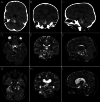

Observations: Here, the authors present the case of a 3-year-old male who presented with hemiparesis and eventually developed hydrocephalus from a giant brainstem cavernous malformation. The patient initially did well on steroids but had a recurrent hemorrhage that led to worsening hemiparesis and hydrocephalus. The authors then elected to resect the cavernous malformation via a supracerebellar infratentorial approach utilizing intraoperative MRI to ensure complete resection. Postoperatively, the patient returned to near baseline neurological function.